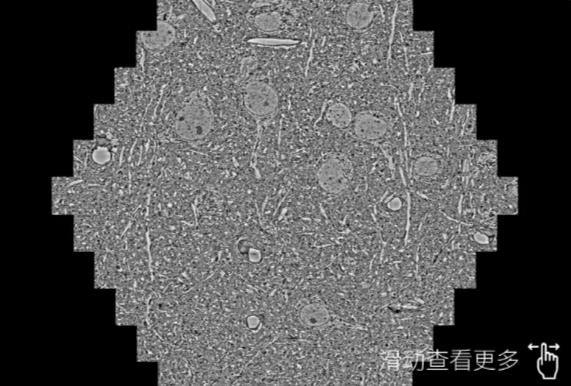

鼠脑切片。左图使用宿迁蔡司宿迁扫描电镜MultiSEM706对165μmx143pm面积区域成像,耗时仅需1.5秒。右图为鼠脑切片中30μm区域放大效果。样品由芝加哥大学B.Kasthuri提供。